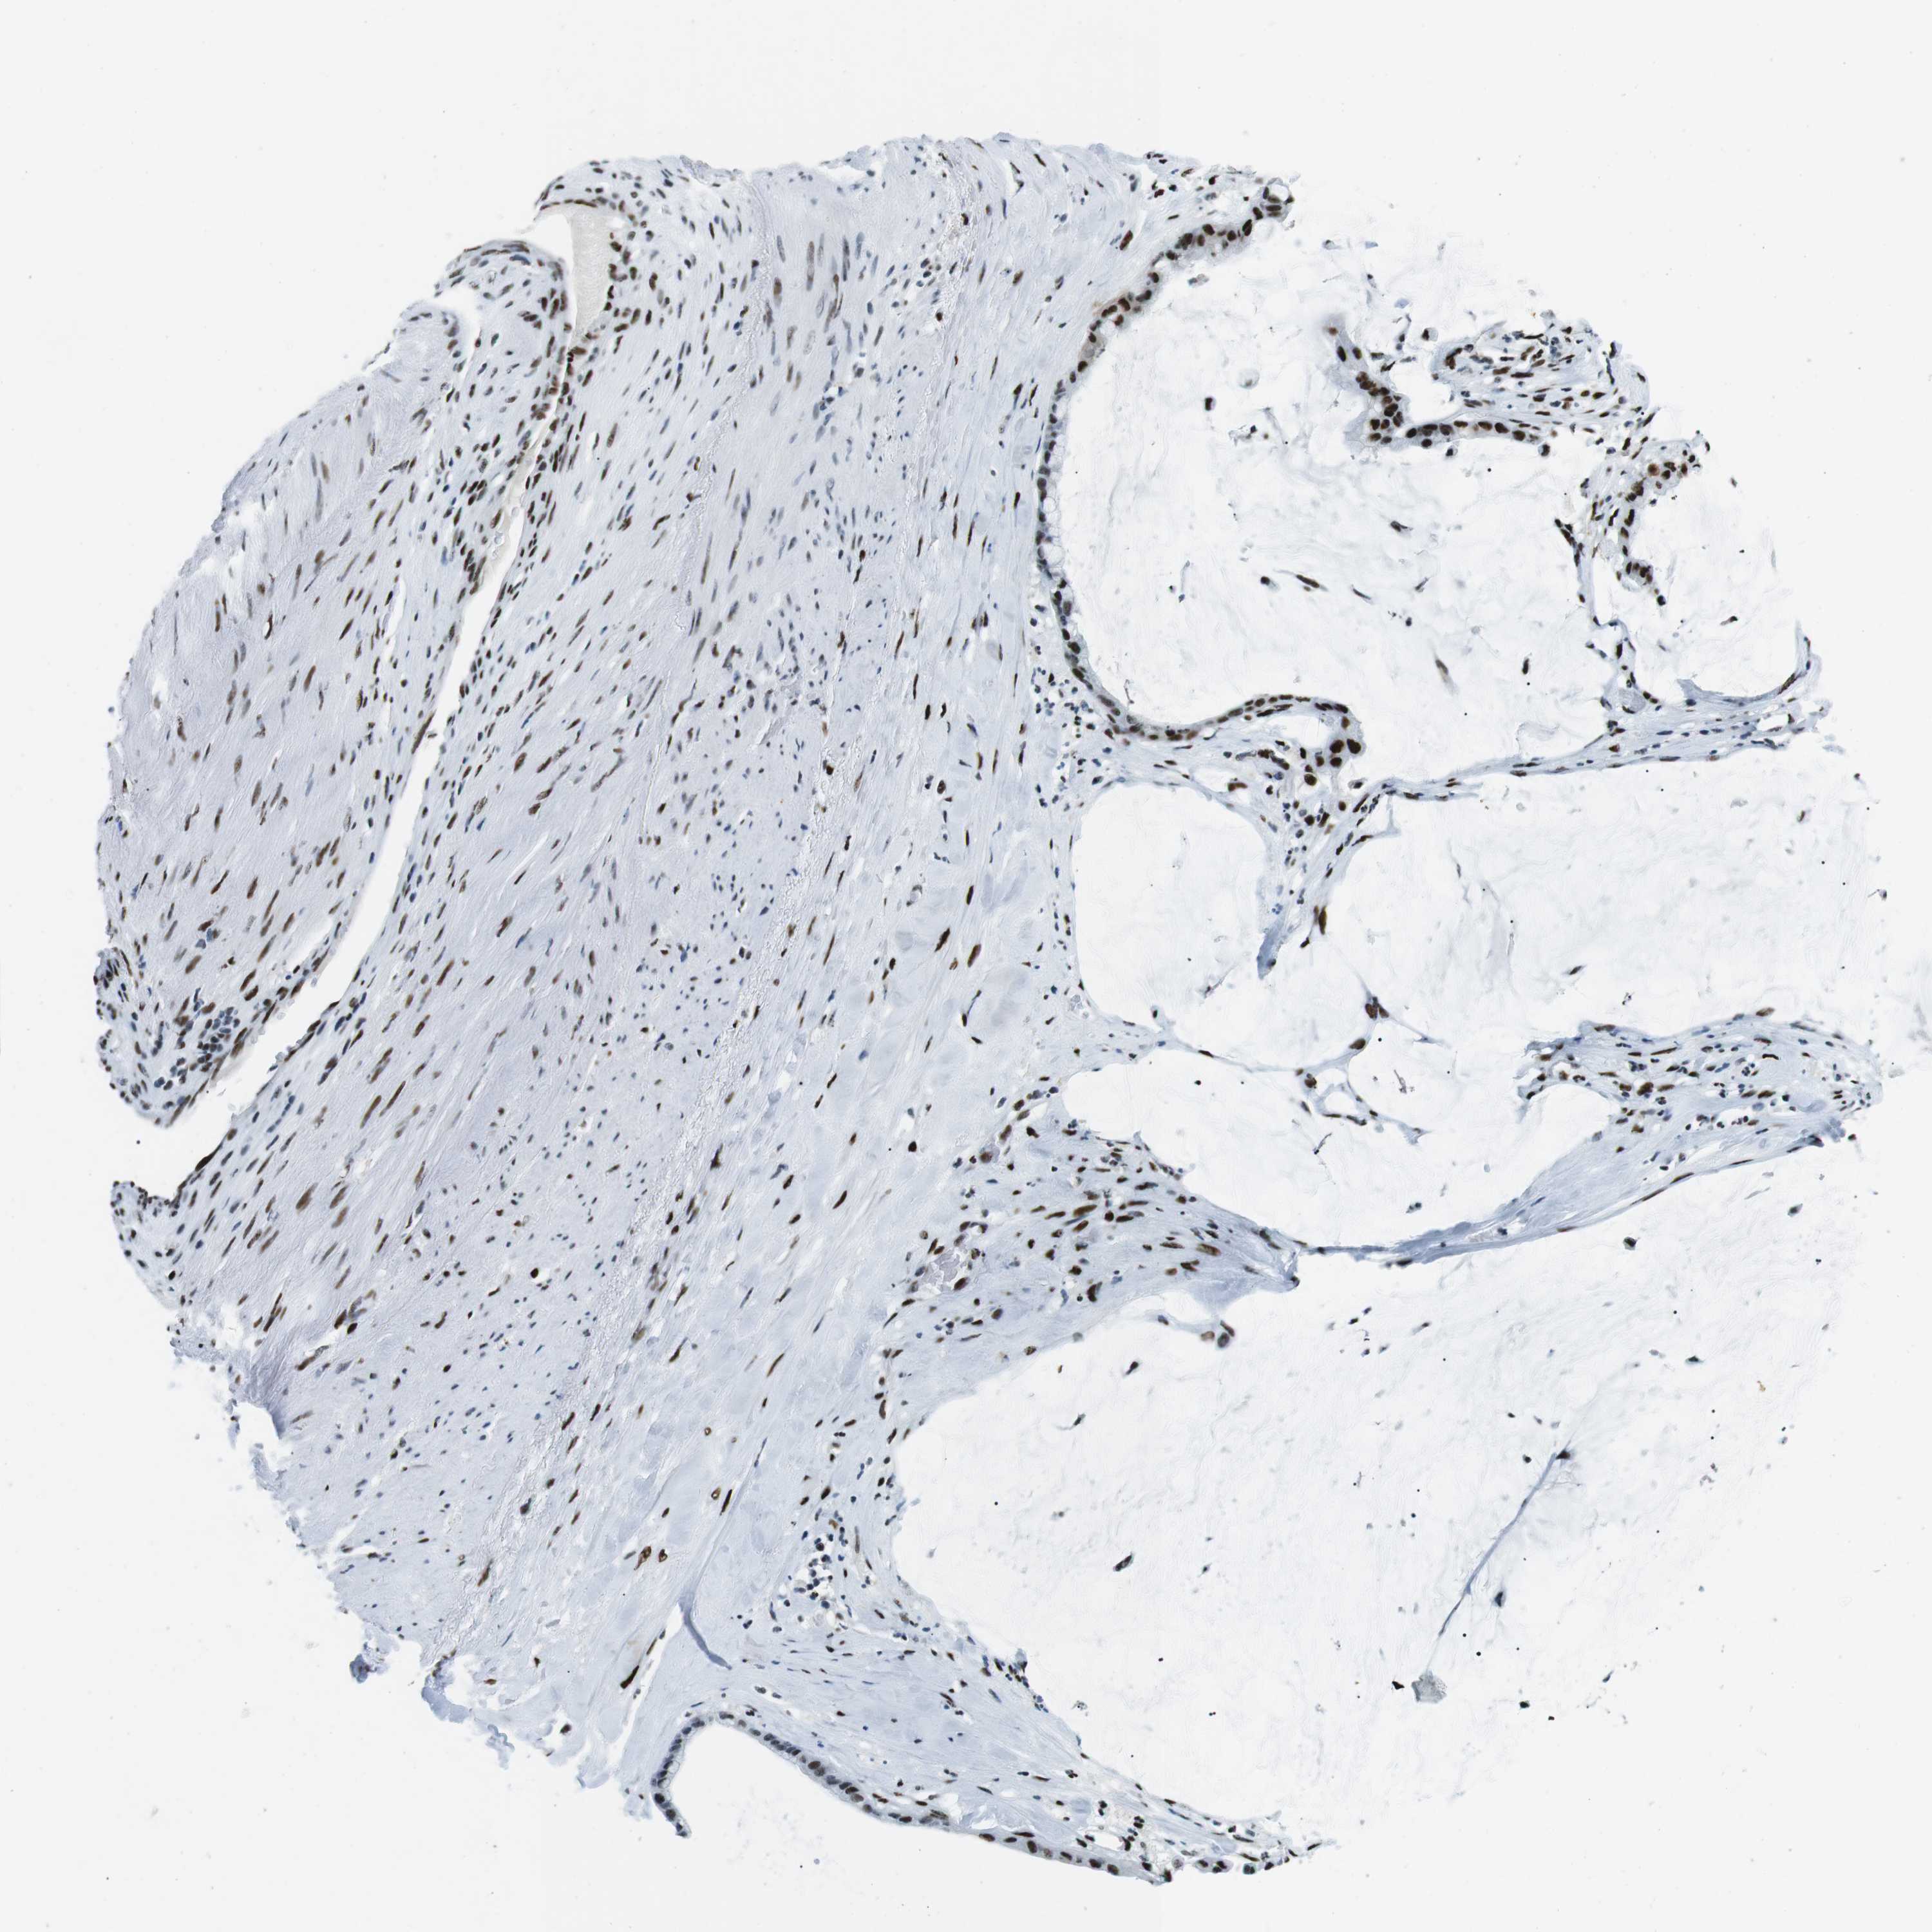

PANCREATIC CANCER - Protein expressioni

A mouse-over function shows sample information and annotation data. Click on an image to view it in a full screen mode. Samples can be filtered based on level of antibody staining by selecting one or several of the following categories: high, medium, low and not detected. The assay and annotation is described here.

Note that samples used for immunohistochemistry by the Human Protein Atlas do not correspond to samples in the TCGA dataset.

Antibody stainingi

Antibody staining in the annotated cell types in the current human tissue is reported as not detected, low, medium, or high, based on conventional immunohistochemistry profiling in selected tissues. This score is based on the combination of the staining intensity and fraction of stained cells.

Each image is clickable and will lead to virtual microscopy that enables deeper exploration of all samples and also displays staining intensity scores, fraction scores and subcellular localization as well as patient and tissue information for each sample.

Antibody HPA008312

Antibody CAB010194

Antibody CAB016304

Staining

High

Medium

Low

Not detected

Intensity

Strong

Moderate

Weak

Negative

Quantity

>75%

75%-25%

<25%

None

Location

Nuclear

Cytoplasmic/membranous

Cytoplasmic/membranous,nuclear

Adenocarcinoma, NOS

Adenocarcinoma, metastatic, NOS